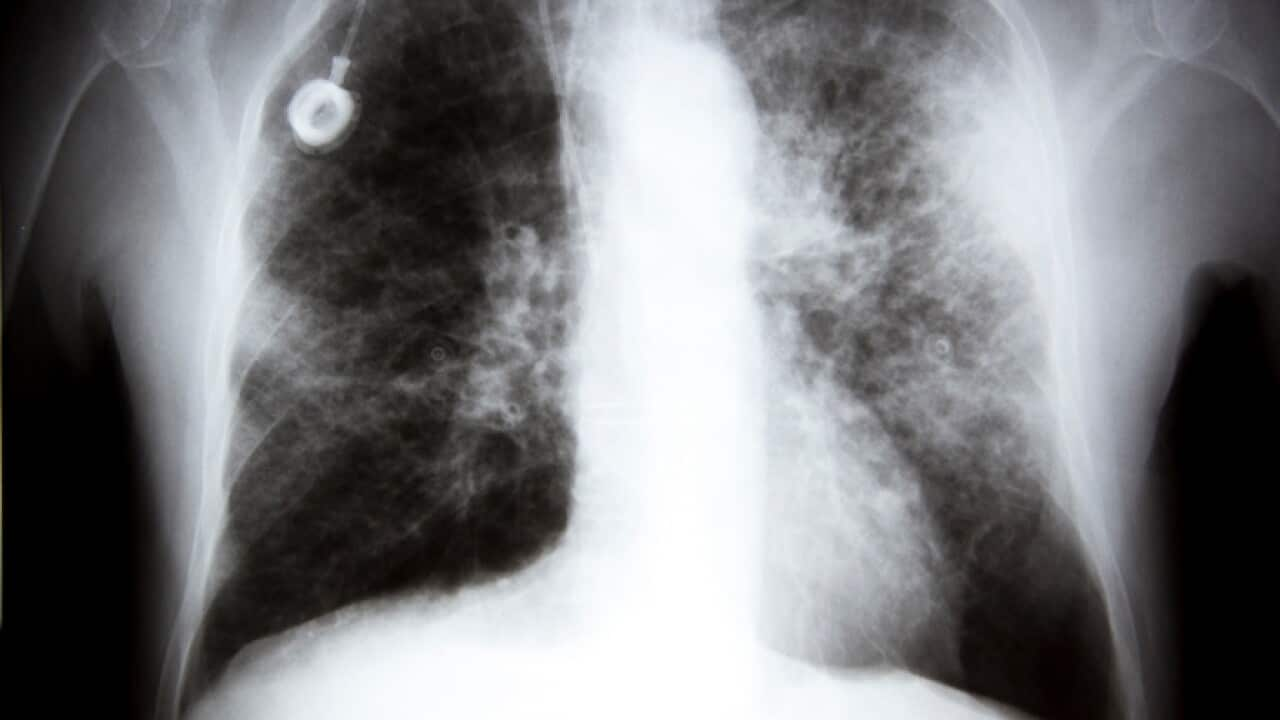

- Mamogram tipik olarak göğüslerin röntgen görüntülerini almayı içerirken, yeni deneme, katılımcıların tükürük ve aile geçmişinden bir örnek vermelerini gerektiriyor.

Bir kişinin meme kanserine yakalanma riskini belirlemek için tükürük kullanilan yeni bir test uluslararası olarak deneniyor. Doktorların, insanların meme kanseri için tarama ve tedavi yöntemlerinde devrim yaratacağını umduğu araştırmaya bir İngiliz hastanesi de katılıyor.